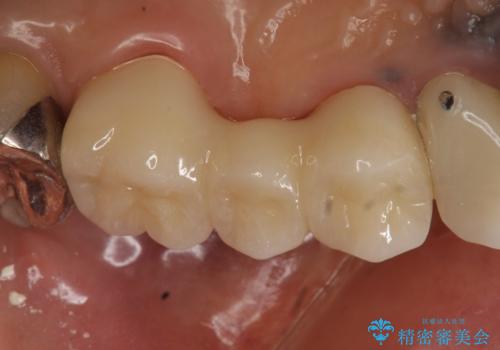

- 昔治療した左上56の延長ブリッジをきちんと治療しなおしたいといらっしゃった方の症例です。

古いブリッジを除去後、オールセラミッククラウンによる補綴を行いました。

今回用いたオールセラミッククラウンは、ジルコニアフレームという白い素材の上にセラミックを盛っているため審美性が非常に高いのが特徴です。

またジルコニアは人工ダイヤモンドの材料にも使われているほど高い強度を持っており、そのためオールセラミッククラウンは審美性だけでなく、奥歯やブリッジの補綴も可能とするクラウンです。